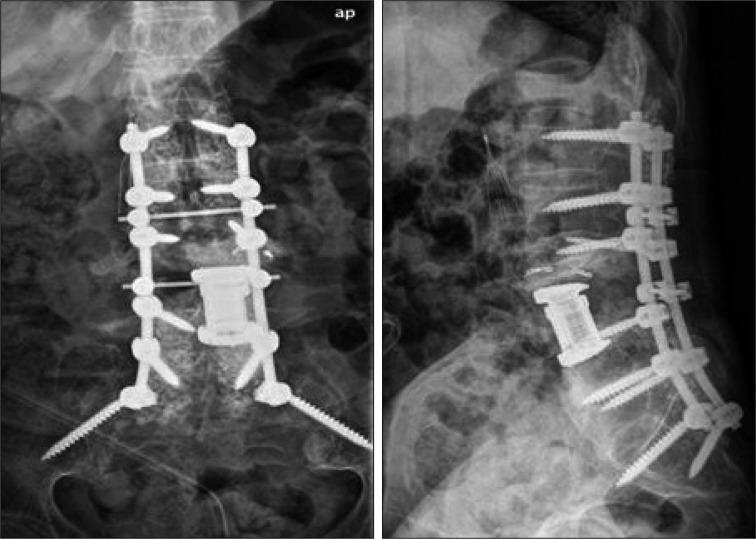

Spinal infection is an inflammatory process around the vertebral body, and it can extend to the epidural space, posterior elements and paravertebral soft tissues. Infectious spondylitis is a rare infectious disorder, which is often associated with significant neurologic deficits and mortality. When an extensive soft tissue defect is accompanied by infectious spondylitis, effective infection control and proper coverage of soft tissue are directly connected to successful outcomes. However, it is not simple to choose the appropriate treatment methods for infectious spondylitis accompanied by a soft tissue defect. Herein, we report a case of severe infectious spondylitis that was accompanied by an extensive soft tissue defect which was closed with a reverse latissimus muscle flap after traumatic spinal epidural hemorrhage.